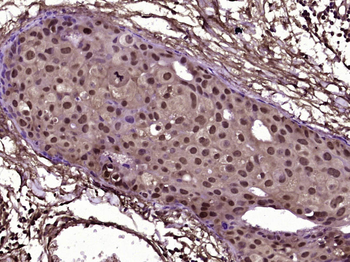

MBD1 Rabbit Polyclonal Antibody

IF, IHC-Fr, IHC-P

应用稀释比例:IHC-P=1:100-500, IHC-F=1:100-500, IF=1:100-500